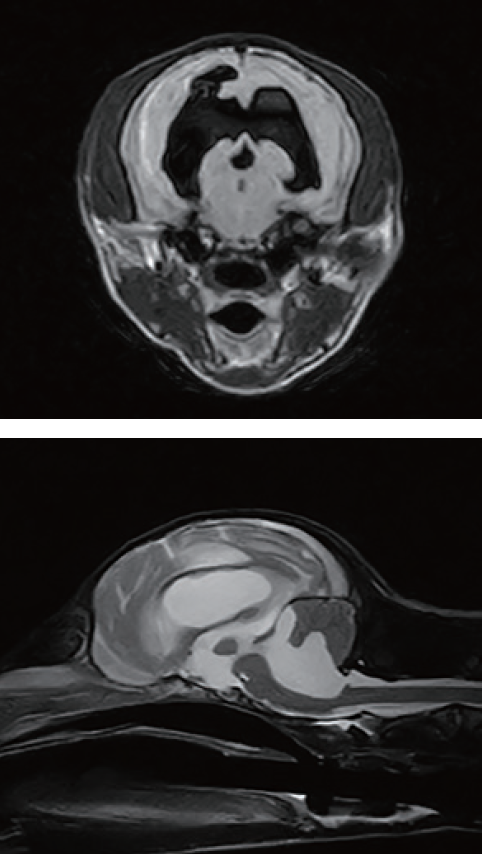

頭部MRI検査より、先天性水頭症、脳挫傷、頚髄挫傷と診断した。 先天性水頭症による進行性の神経症状が基礎にあり、脳挫傷、頚髄挫傷は階段から落下したことに起因する続発障害であると判断した。

受傷後48-72hは特に急性増悪に警戒しながら内科治療を行った。その後の安定期においても、不全麻痺、認知障害、活力低下などが持続し、先天性水頭症の影響が強く示唆され、来院11日目にV-Pシャント術を実施した。

臨床的にも明らかな改善を認め、術後11日目に退院したが、退院10日後に、活動性の低下、流涎を呈し再来院した。皮下に埋めたバルブを触診すると、カテーテルの閉塞が疑われた。CSFの流路障害、排液不良による脳室内のCSF增加、脳圧亢進が原因と考えられた。カテーテルの閉塞は用手で皮下のバルブのポンピングにて解除を行った。同時に抗菌薬を主体とした、支持療法を行った。3日後に症状の改善と再閉塞が無い事を確認し、退院した。